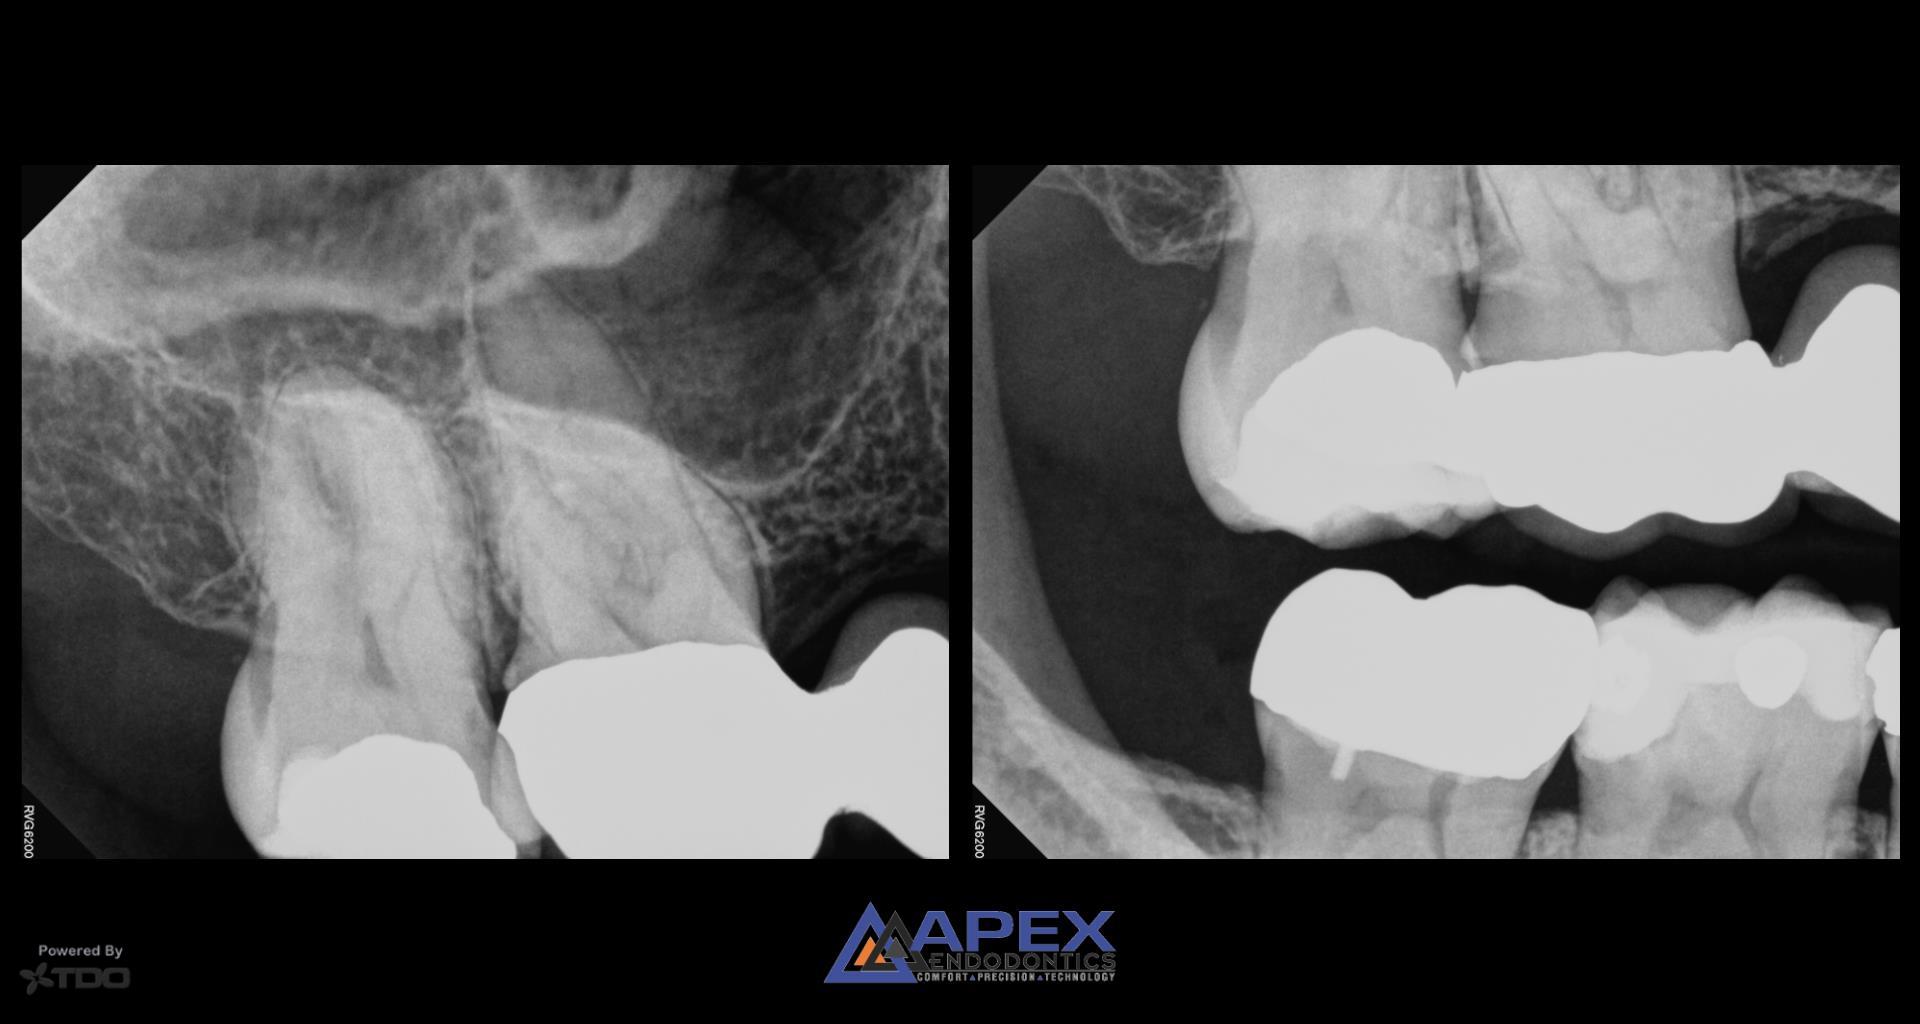

From www.apexendoco.com

Case Study Cracking The Case of Tooth Sensitivity to Heat in Tooth 3 Why Is My Tooth Sensitive To Heat But it can also mean that you have a. A tooth that is sensitive to heat or cold may need root canal treatment. Tooth sensitivity occurs when the enamel wears off and exposes the dentin, which reacts to heat and cold. Learn why this happens, what to expect from your dentist or endodontist, and how to prevent. The american academy. Why Is My Tooth Sensitive To Heat.